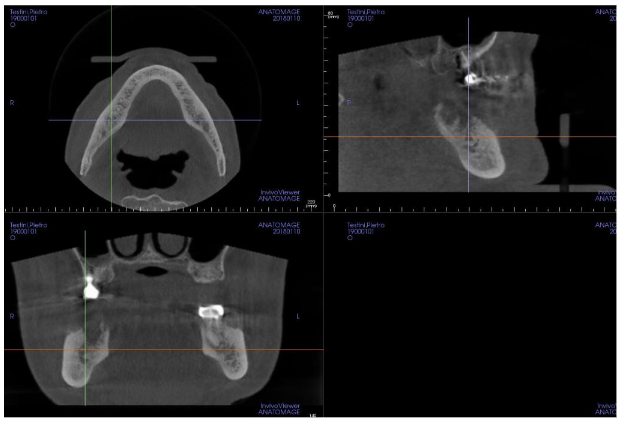

The lesion showed necrotic bone mixed with other parts in rapid growth: the cavity arrived so much deep that the lesion interested the lower alveolar nerve, causing a continuous, severe and burning pain interesting the mandible and radiated to the right ear, causing a worsening of the patient’s quality of life. Since his clinical conditions were very compromised above all for a severe heart failure it was decided to avoid any surgical approach, and the applied therapy was just a local disinfection and antibiotic drugs in case of infection. Moreover the patient used a lot of drugs (furosemide 125 mg twice a day, acetilsalicilic acid 100 mg once a day, Ivabradine 2.5 mg twice a day, Canrenone 50 mg a day, Silodosin 8 mg once a day and pantoprazole 40 mg once a day), and above all he used zolendronic acid (Zometa®) to control the bone metastasis growth derived from the prostatic cancer: this condition increased the risk to have a BRONJ as a postsurgical complication. However, for a continuous worsening of the symptoms and for the several infections of the mandibular lesion we decided, in agreement with his relatives, to surgically remove the gingival lesion cleaning the bone cavity with a conservative approach. To reduce the risk of postsurgical infections and of a bad healing (due to the zolendronic acid and the clinical conditions of the patients) we decided to fill the residual cavity with PRGF®-Endoret® autologous membranes, a particular platelet concentrate that improves and stimulates the healing processes inducing a good tissue regeneration. The Cone Beam Computer Tomography (CBCT) showed the extension of the bone lesion (images 3-4).